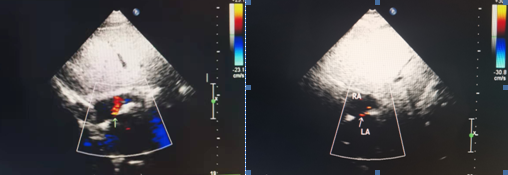

经临床医生判断,齐医附属二院超声科为李先生安排了右心声学造影检查。从下图可知,本来有一墙之隔的左心房和右心房间,出现了一个“通道”,这个“通道”就是未关闭的卵圆孔,它使得大量气泡从右心到达左心。原来,造成李先生多年头痛不断的罪魁祸首就是这个原本应该关闭的卵圆孔。

超声科团队为李先生进行右心声学造影检查

卵圆孔未闭的常规心脏超声检查可见房间隔中部左向右红色过隔血流信号,如下图。